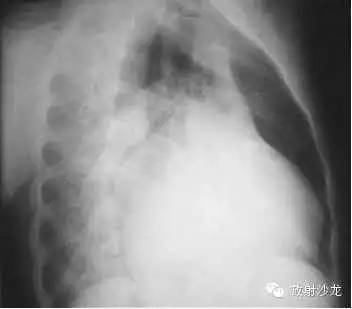

X线表现为心脏增大,肺淤血,间实质肺水肿,胸腔积液

左房右室增大

1、心脏向两侧增大,正常心缘弧度消失。

2、腔静脉增宽(体静脉回流右房受阻)。

3、心脏血管比率增大,主动脉影缩短。

4、心缘搏动下降,主动脉搏动正常。

5、肺纹理减少或正常(右心排血量减少)。